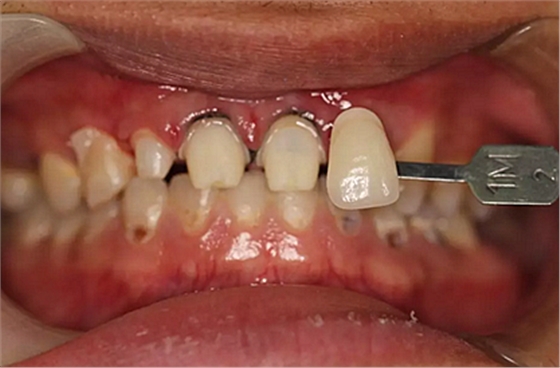

第二次治療是半個月后,這次做了根管充填后將覆蓋在我們身體上的一部分牙齦切除,讓我們埋于牙齦下的身體暴露了一部分,也就是醫(yī)生說的冠延長術。這是為了讓我們變得美觀一些。

冠延長術